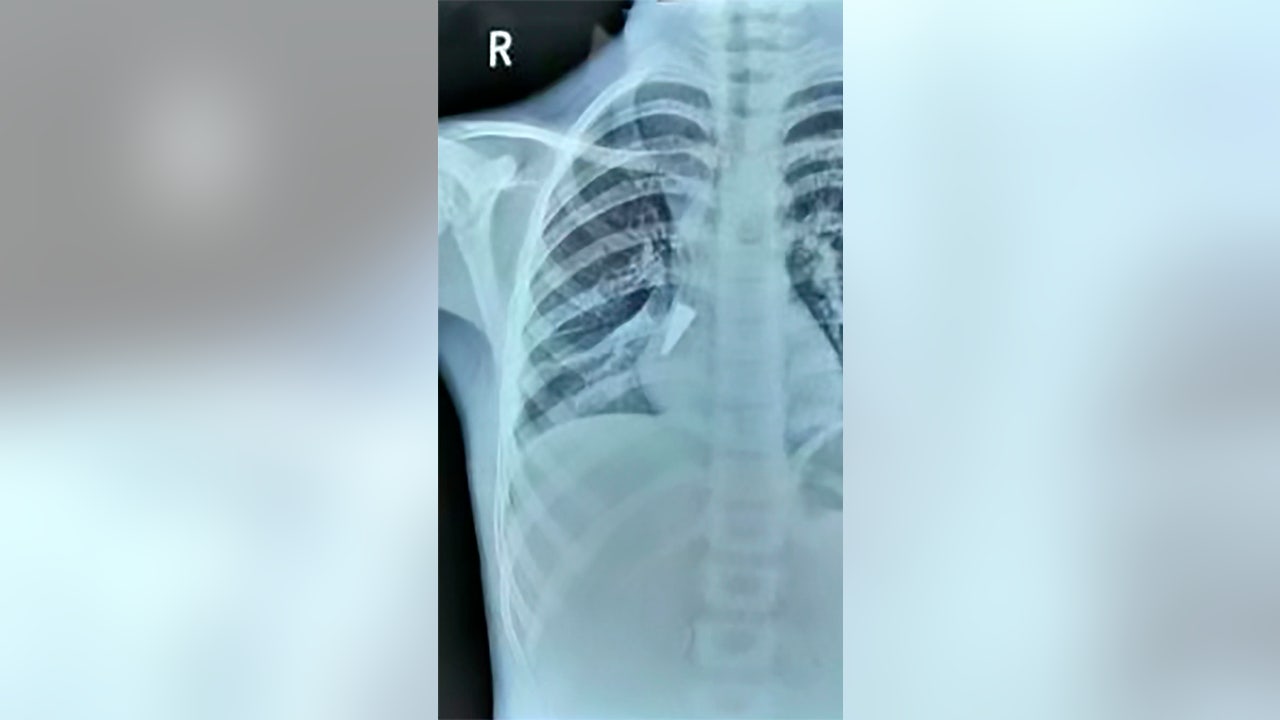

A scan showing the metal pen cap in the girl's lung. (AsiaWire)

She allegedly suffered from a cough for three weeks, which prompted her grandfather to seek medical help for the girl at First People’s Hospital of Xiangyang, according to AsiaWire. She was admitted to the pediatric ward where Dr. Yang Wu ordered scans and found the .8-inch cap in her right lung.